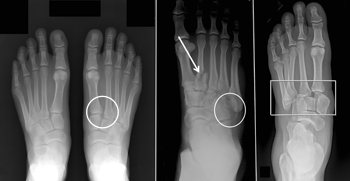

(Left) This is a subtle injury to the midfoot with widening between the first and second metatarsals (circle), compared with the normal foot on the left. (Center) This x-ray shows a fracture of the second metatarsal (arrow) and a fracture of the cuboid (circle). (Right) This shows a very severe injury of the foot from a high-energy event. It has resulted in a complete dislocation of the entire midfoot (box). Because no bones have been broken, a fusion may be recommended, given the high risk for future arthritis.